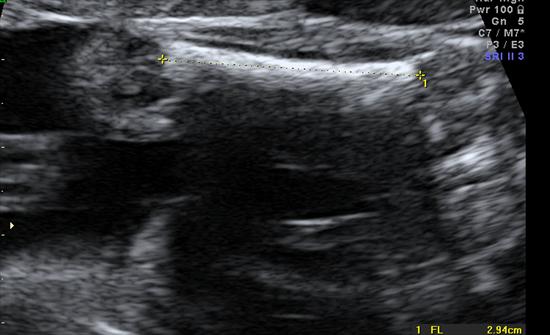

Attachment 19003

or this one from the 19week scan...